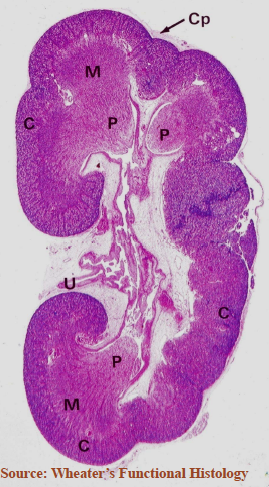

Identify the tissue.

kidney

What are the two main regions of the kidney?

cortex & medulla